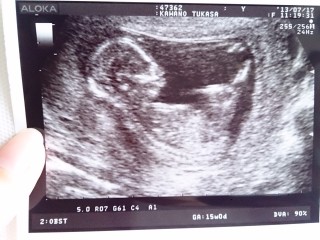

15W0D 初めての3Dエコー。 胸の前で両手をクロスして、座っているような格好。可愛い~!今日のエコーでは男の子と判明しました。 推定体重は140g。これからドンドン大きくなっていくんだろうなぁ。楽しみ!!

頭の大きさは2.94cmでした。

15週のときのエコーです。全身きれいに写っていてお気に入りの1枚です。週数が進んでもこの顔を隠しているショットが多いです(笑)